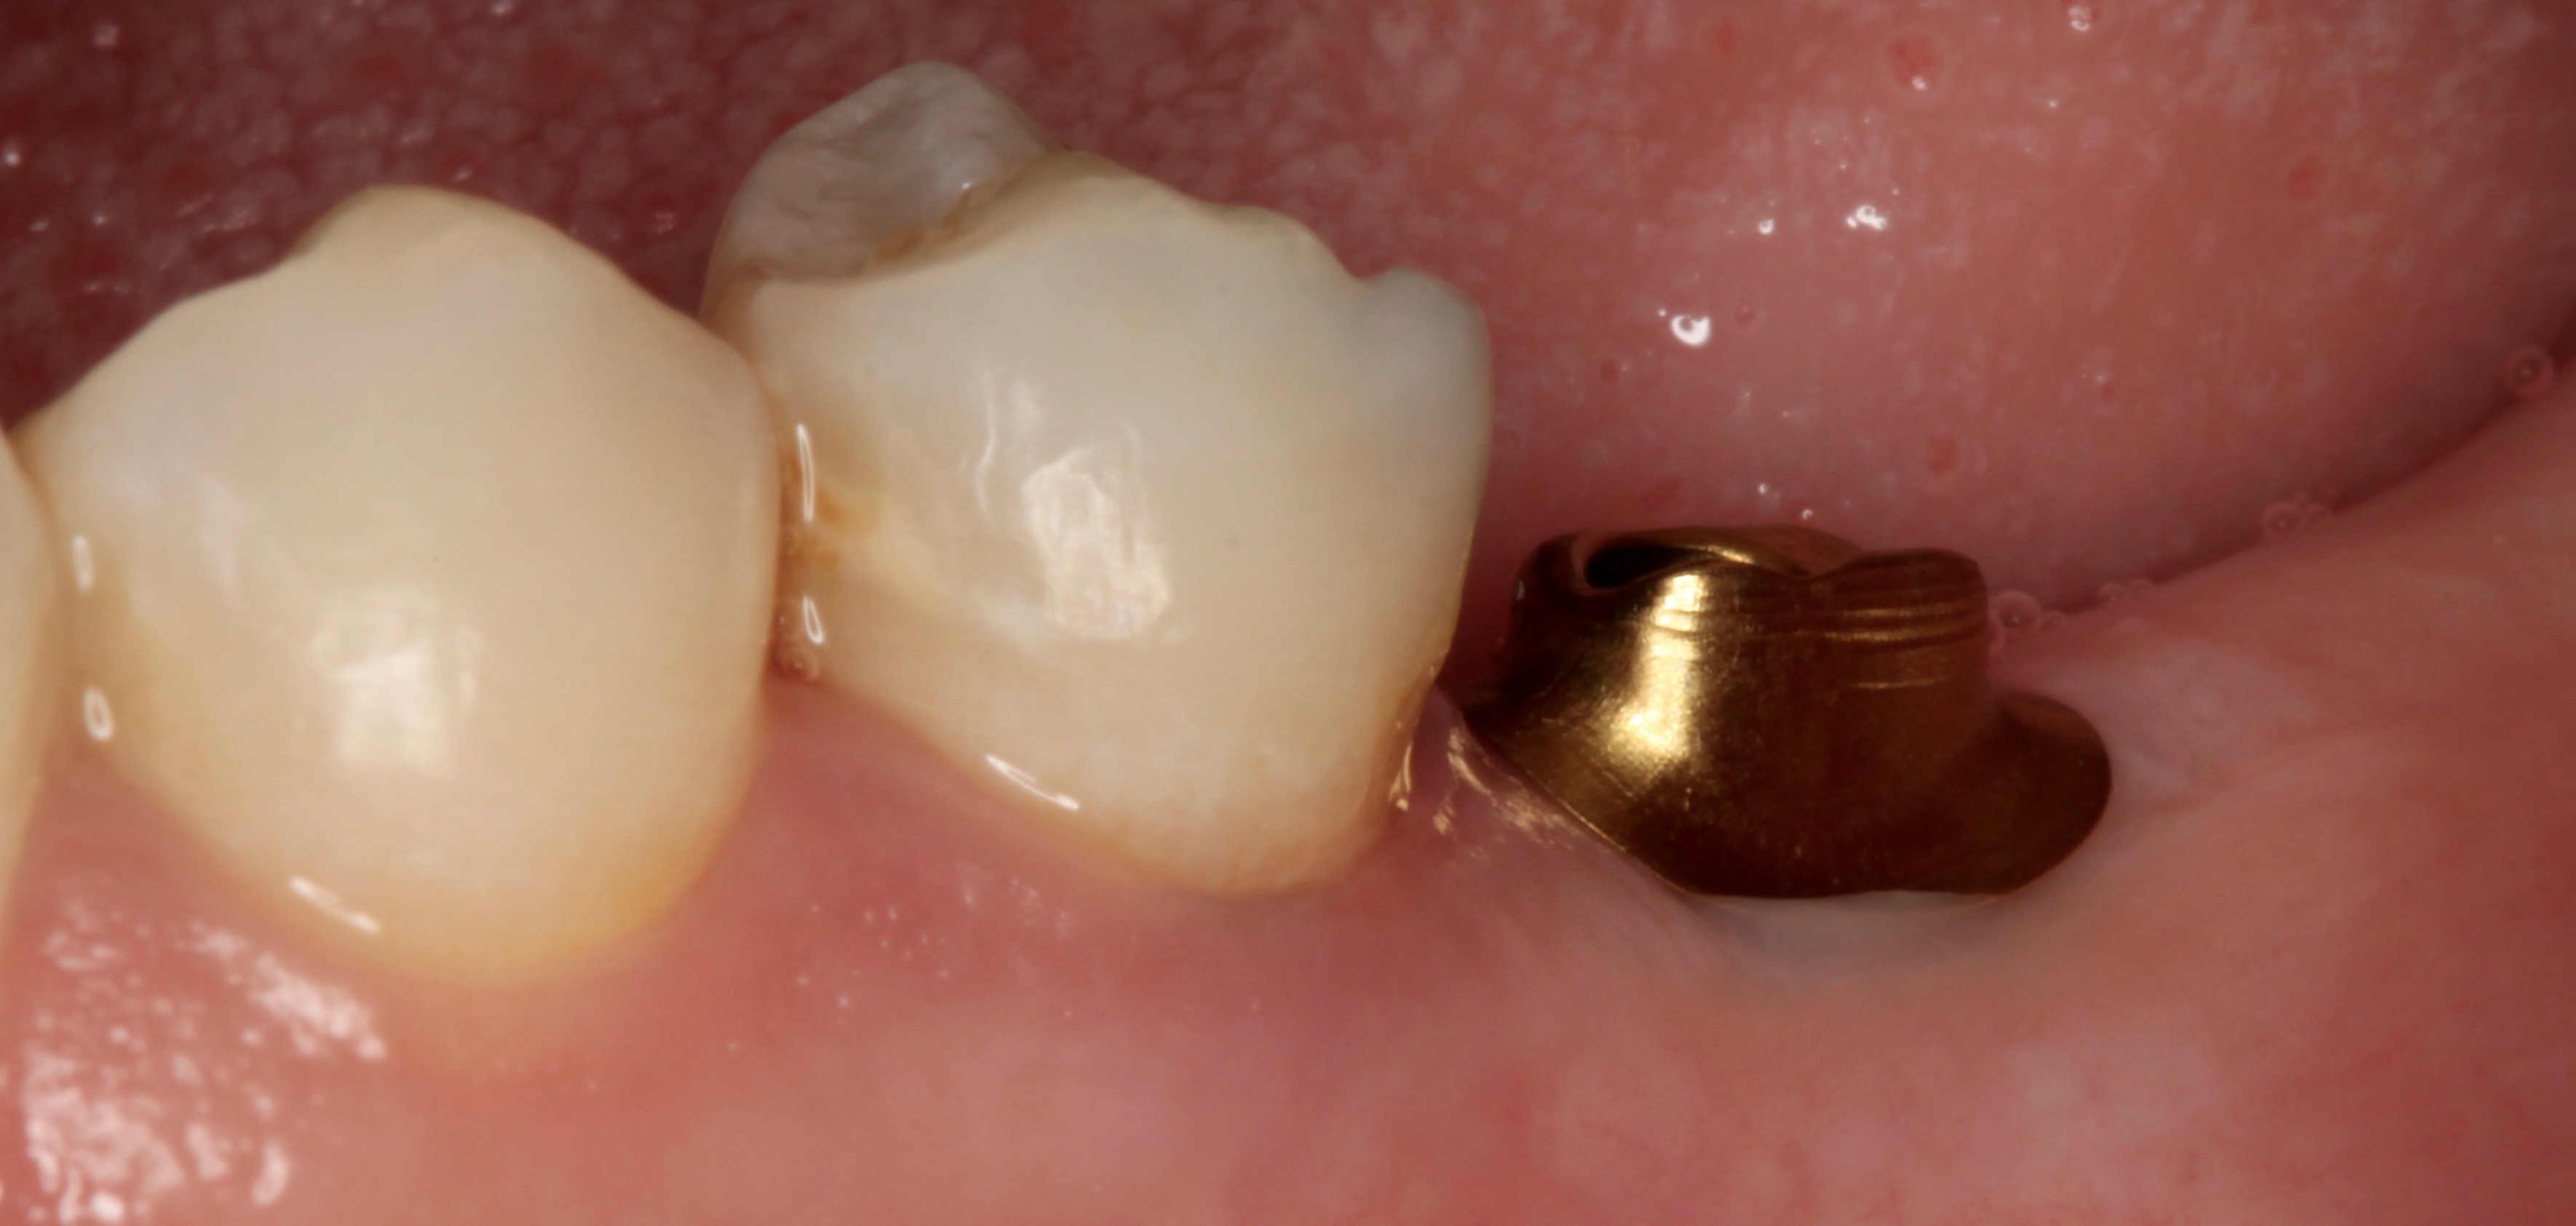

Integrative digital planning can also lead to quicker and more efficient treatment times for dental implant therapy. Another patient presented for a dental implant to replace tooth No. 19 at the end of orthodontic treatment. By leveraging 3D planning (Figure 13) and the printing of a surgical guide, the patient's implant was placed using a flapless approach. At the time of placement, an intraoral scan body was placed on the implant and digital impressions were made for her final restoration (Figure 14). At 10 weeks, the final custom abutment and CAD/CAM crown were delivered, all digitally fabricated without the use of physical models (Figure 15 through Figure 17). For implant placement and restoration, the patient had two visits, with a total chair time of 65 minutes, and no need for anesthetic at the second visit.

Fig 14. Scan body after No. 19 implant placement.

Figure 14